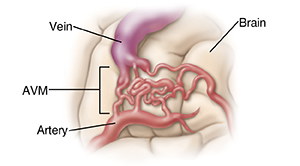

Normally, arteries carry blood with oxygen from the heart to the brain and veins carry blood with less oxygen away from the brain. However, an AVM results in a tangle of blood vessels in the brain. This tangle bypasses brain tissue and sends blood directly from the arteries to the veins. It's important to get medical attention for an AVM as soon as possible. Often, immediate treatment may help prevent serious complications of some AVMs. Current surgical methods make treatment for AVM safer and more effective than ever. The goal of treatment is to stop the flow of blood within the AVM and to prevent it from re-bleeding.